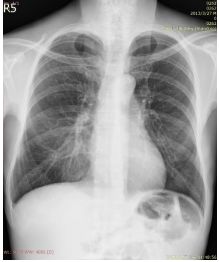

1. A 39-year-old man had this chest X-ray on his health exam. No any clinical symptoms.